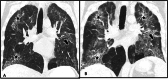

Hermansky-Pudlak syndrome (HPS) is a genetic multisystemic disorder with oculocutaneous albinism, granulomatous colitis, bleeding diathesis, and pulmonary fibrosis. Multiple subtypes of HPS exist, with certain types having higher predilection for pulmonary fibrosis. This case report focuses on the demonstration of pulmonary imaging findings seen in a patient. Several imaging features overlap with idiopathic pulmonary fibrosis including traction bronchiectasis, pleural and peribronchovascular thickening, and reticulations. This case report highlights the differences seen in lung disease associated with HPS compared to other interstitial lung diseases, in addition to the multi-systemic features of HPS.